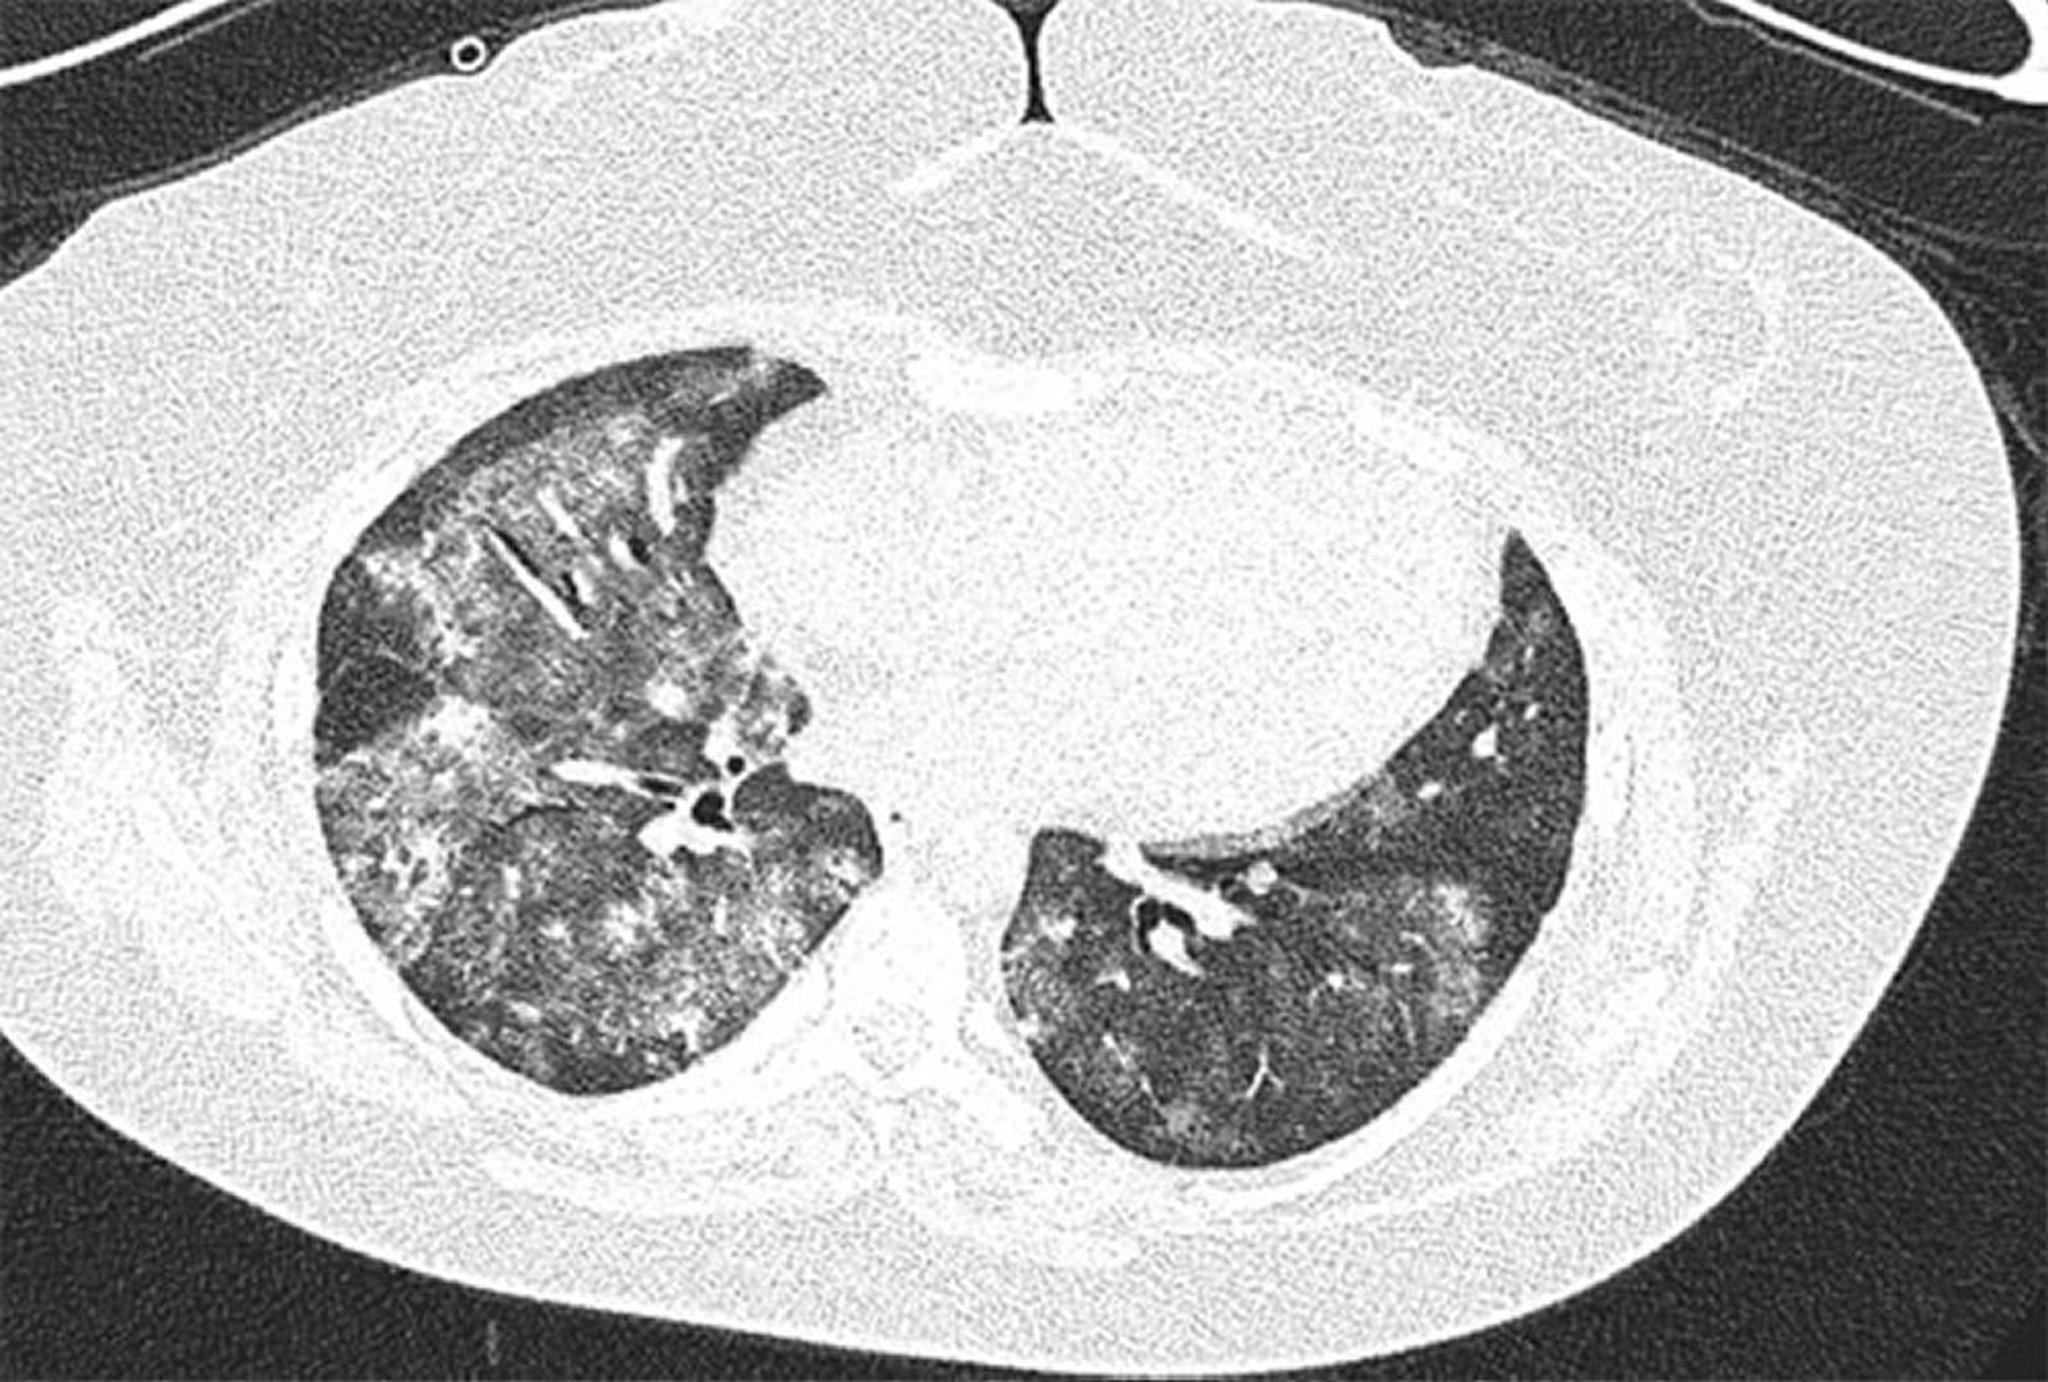

Диффузное альвеолярное кровотечение

КТ-скан высокого разрешения 28-летней женщины с антифосфолипидным синдромом с рецидивирующим диффузным альвеолярным кровотечением. Изображение показывает двусторонние и очаговые уплотнения в альвеолах по типу матового стекла, с сохранностью в субплевральной зоне. Бронхоальвеолярный лаваж подтверждает альвеолярное кровотечение.

Image courtesy of Joyce Lee, MD.